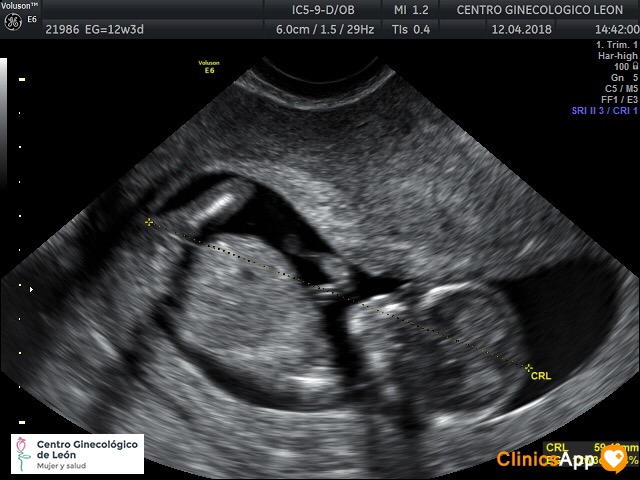

Ecografías del 12 de abril de 2018